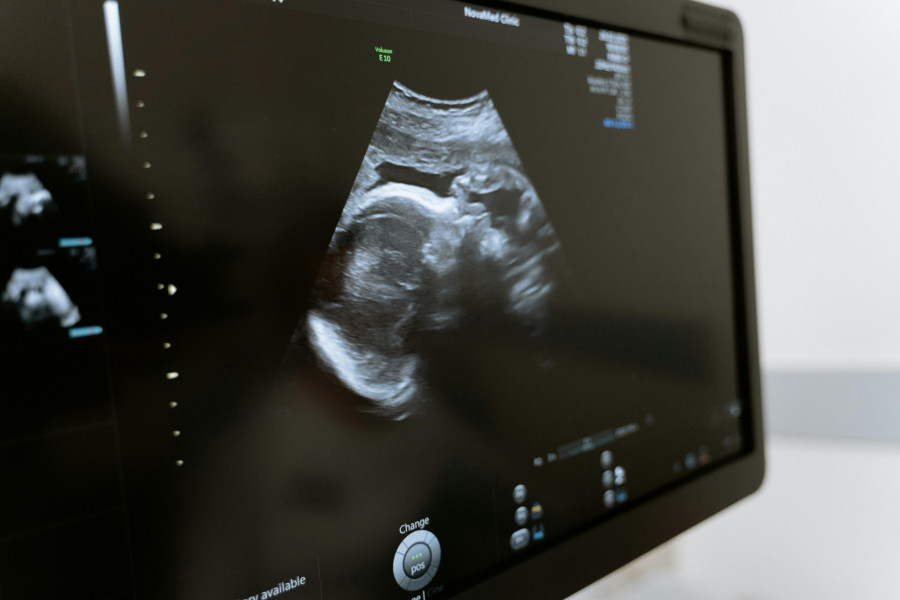

Τέλος μπήκε σε μια αναμονή σχεδόν δύο δεκαετιών για ένα ζευγάρι που προσπαθούσε να κάνει παιδί. Οι γιατροί στο Κέντρο Γονιμότητας του Πανεπιστημίου Κολούμπια ανακοίνωσαν αυτό που αποκαλούν την πρώτη εγκυμοσύνη με τη βοήθεια ενός νέου συστήματος τεχνητής νοημοσύνης, σε ένα ζευγάρι που προσπαθούσε να αποκτήσει παιδί για πάνω από 19 χρόνια.

Σε μια πρωτοποριακή εξέλιξη στον τομέα της αναπαραγωγικής ιατρικής, οι ερευνητές ανέφεραν την πρώτη επιτυχημένη εγκυμοσύνη με τη χρήση μιας καινοτόμου διαδικασίας βασισμένης στην τεχνητή νοημοσύνη, γνωστής ως STAR (Sperm Tracking and Recovery).

Από την υπογονιμότητα στη γονεϊκότητα

Η σημασία αυτής της ανακάλυψης, που συνδυάζει την ιατρική επιστήμη με τις τεχνολογίες αιχμής, ενισχύεται από την ιστορία του ζευγαριού που προσπαθούσε να συλλάβει για σχεδόν είκοσι χρόνια. Παρά τις 15 αποτυχημένες προσπάθειες εξωσωματικής γονιμοποίησης, τα πράγματα άλλαξαν όταν συμμετείχαν σε μια κλινική δοκιμή με το σύστημα STAR. Η τεχνολογία που στηρίζεται στην τεχνητή νοημοσύνη εντόπισε βιώσιμο σπέρμα και οδήγησε σε επιτυχημένη εγκυμοσύνη – ένα ορόσημο που τους διέφευγε για χρόνια.